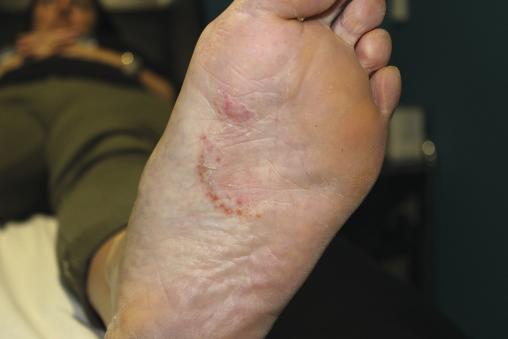

Monique, 63 ans, consulte pour une lésion prurigineuse apparue au niveau de la plante du pied, résistante aux dermocorticoïdes. Circulaire, ses bords sont délimités par un bourrelet constitué de vésicules et d’éléments hyper- kératosiques.

– dyshidrosique : lésions circinées prurigineuses dont les bordures sont constituées de vésicules qui sèchent et forment une collerette cornée.